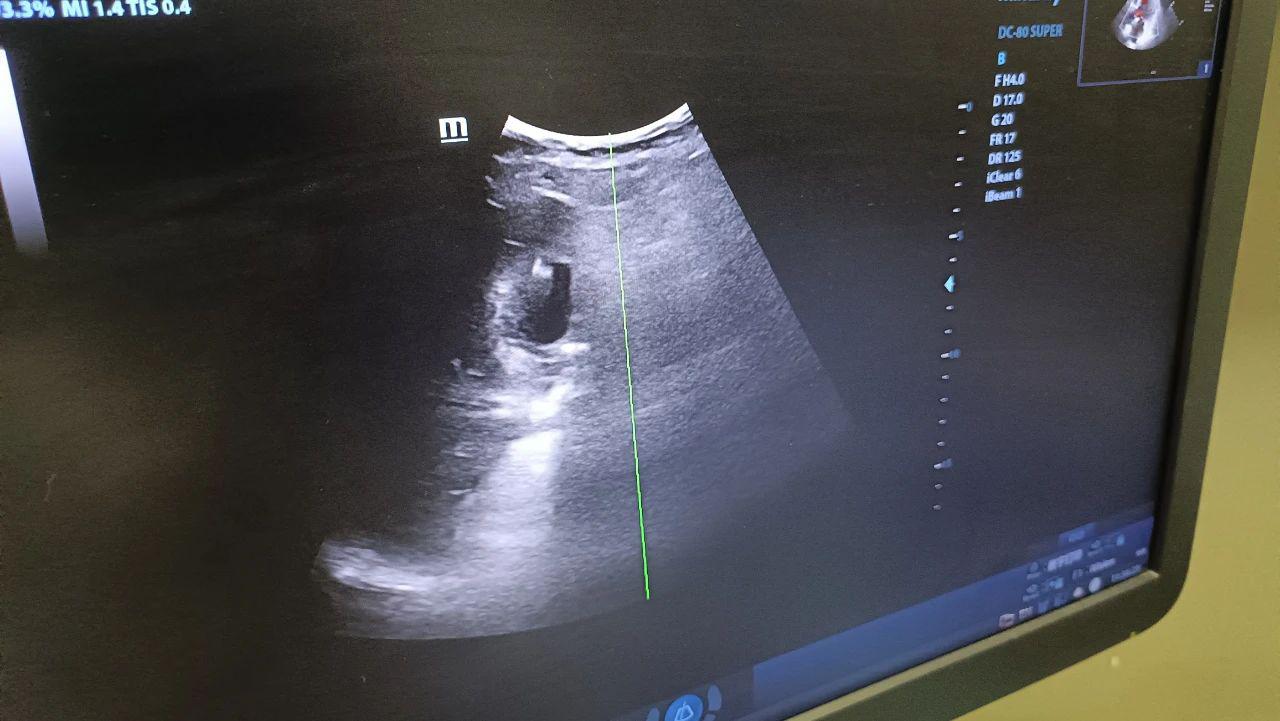

日前,87岁的高大娘,突发急性胆囊炎,紧急来到洛阳白马医院。由于患者高龄,并有严重的心脏病,心率只有38次/分,胆囊结石嵌钝,胆囊梗阻化脓,必须手术。普外科的吕伟子主任、苏东医生对高阿姨的情况进行了系统的分析与讨论,但考虑到手术禁忌,最终决定为她实施超声引导下经皮胆囊穿刺置管引流术(PTGD)。

超声引导下经皮胆囊穿刺置管引流术(Percutaneous Transhepatic Gallbladder Drainage, PTGD)是一种通过超声定位引导,经皮经肝穿刺胆囊并置入引流管,引流淤积的胆汁及脓液,从而缓解胆囊壁水肿、缺血,控制感染进展以缓解胆囊急性炎症、降低胆囊内压力的微创介入技术。该技术具有操作简便、创伤小、安全性高的特点,尤其适用于高龄、合并严重基础疾病或无法耐受外科手术的急性胆囊炎患者。

在与患者及家属进行充分沟通并取得同意后,我院普外科吕伟子主任,苏东医生。在超声科王英主任的全力协助下,成功完成了超声引导下胆囊穿刺置管术。患者无明显不适,术后恢复良好。